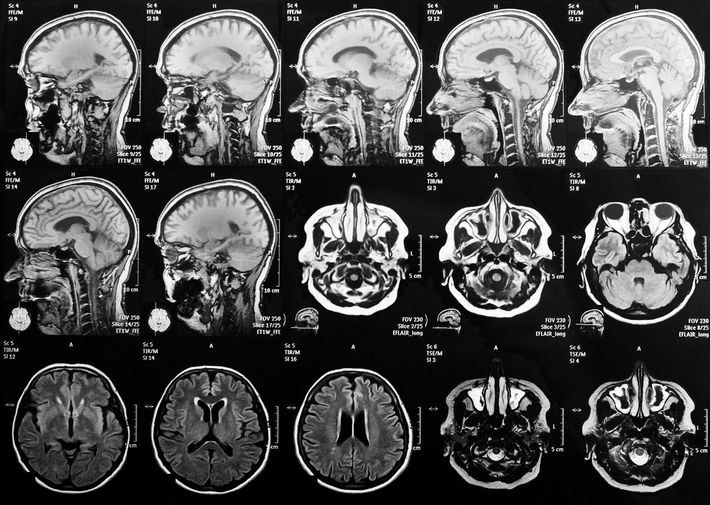

※写真はイメージです